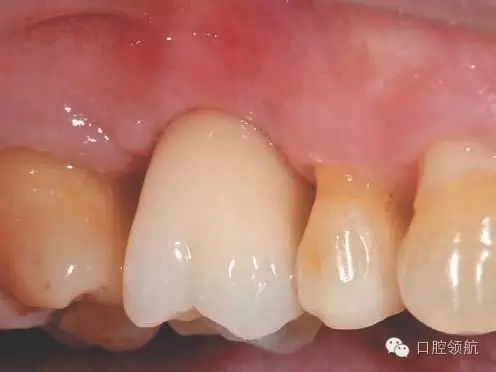

圖2 拔牙后4周,牙齦上皮完全覆蓋拔牙窩。

圖8 術后16周戴入上部修復體。